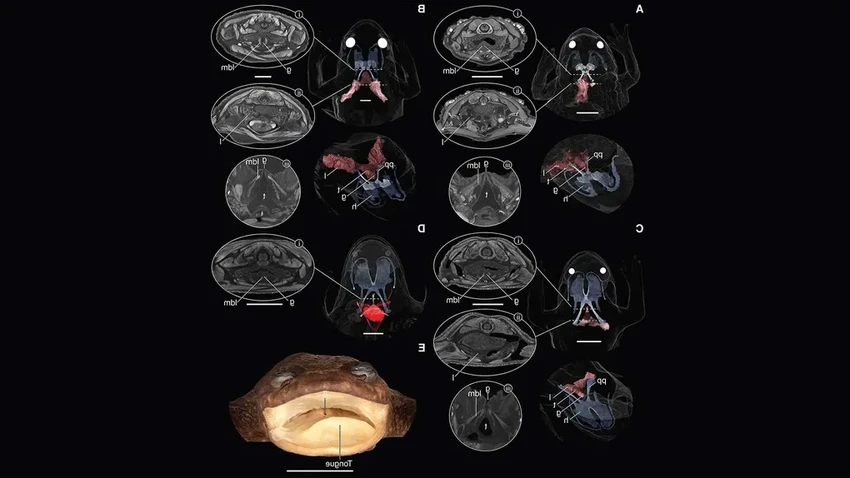

В новом исследовании, опубликованном в журнале Current Biology, учёные из Флоридского университета взялись за дело основательно. Они использовали микроКТ-сканирование — это как рентген, но с невероятной детализацией. Объектом стали два музейных экземпляра той самой «безлёгочной» лягушки.

И технология не подвела: лёгкие нашлись! Правда, размеры их поражают. Если бы их можно было надуть, они бы и вправду уместились под ногтем мизинца. Смешно, да? Полтора десятилетия мы думали, что их нет, а они просто прятались, будучи микроскопическими.

Так зачем же они ей, если они такие бесполезные для дыхания? Учёные предполагают, что эти крошечные пузырьки служат скорее как балласт и гидролокатор. Они помогают лягушке контролировать плавучесть в стремительных потоках и, возможно, улавливать звуковые вибрации в воде. Основное же дыхание по-прежнему осуществляется через кожу. Получается, она не совсем обманщица, просто её лёгкие выполняют совсем другую работу.